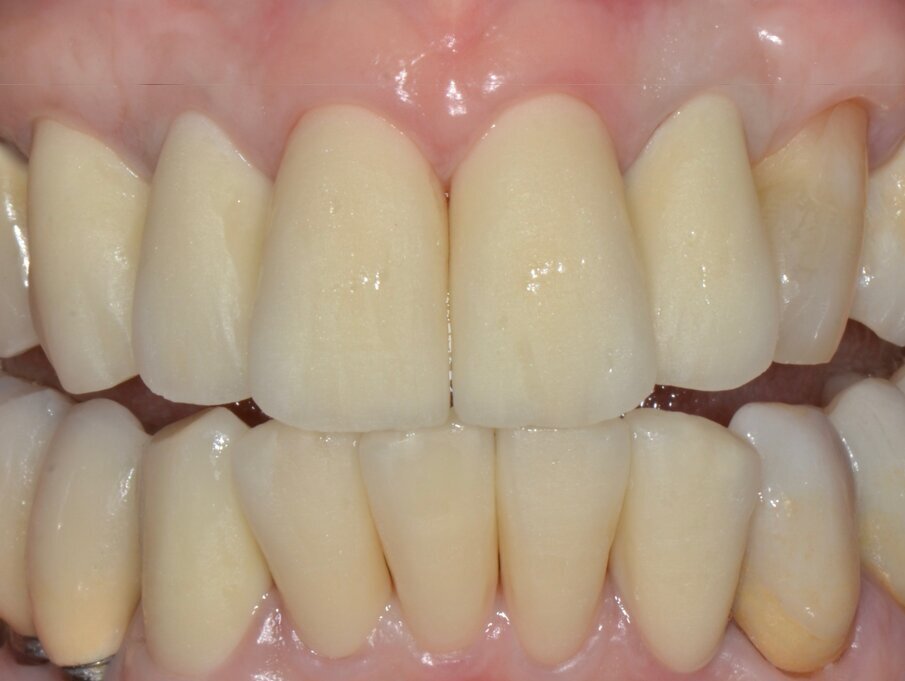

La successiva prova clinica è quella delle ceramiche a biscotto durante la quale viene valutata l’occlusione, la fonetica e l’estetica (Figg. 30-33). Durante la stessa seduta viene eseguita la preparazione per la faccetta in disilicato di litio per il canino superiore sinistro che viene rilevata insieme con l’impronta di rimontaggio delle corone superiori. Una faccetta in resina sul canino viene ribasata e solidarizzata al provvisorio superiore (Figg. 34). La settimana successiva i manufatti finiti vengono provati, cementati adesivamente e vengono eseguite le radiografie finali di controllo (Figg. 35-47).